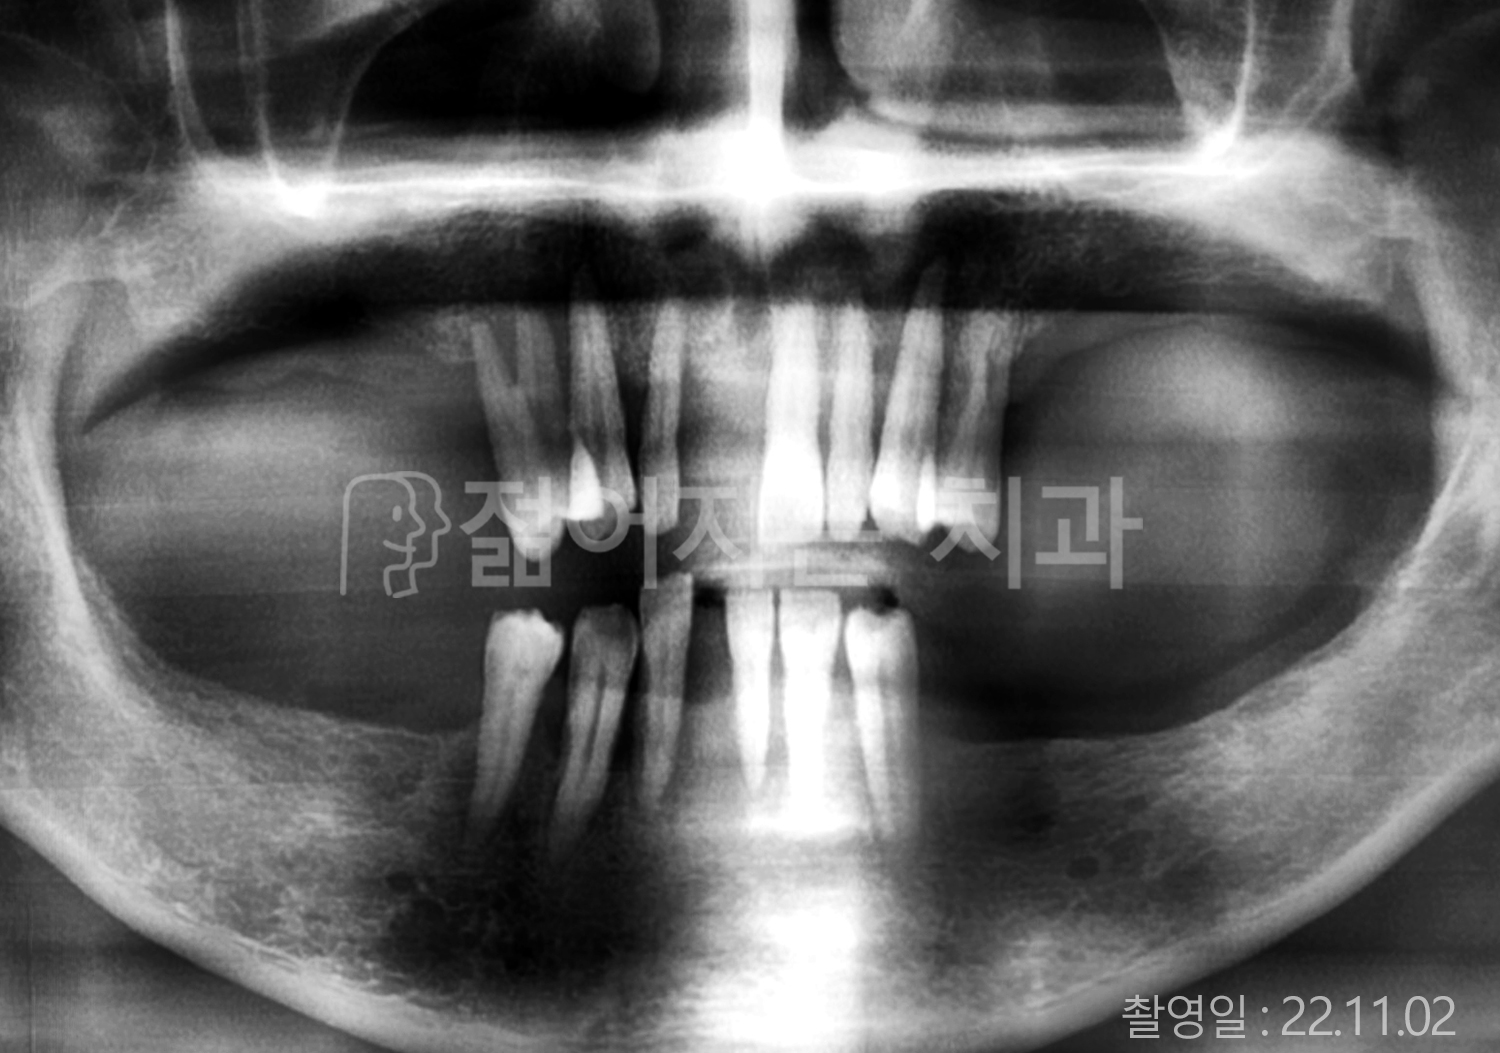

• 50대 전체치아 10개 이상 임플란트